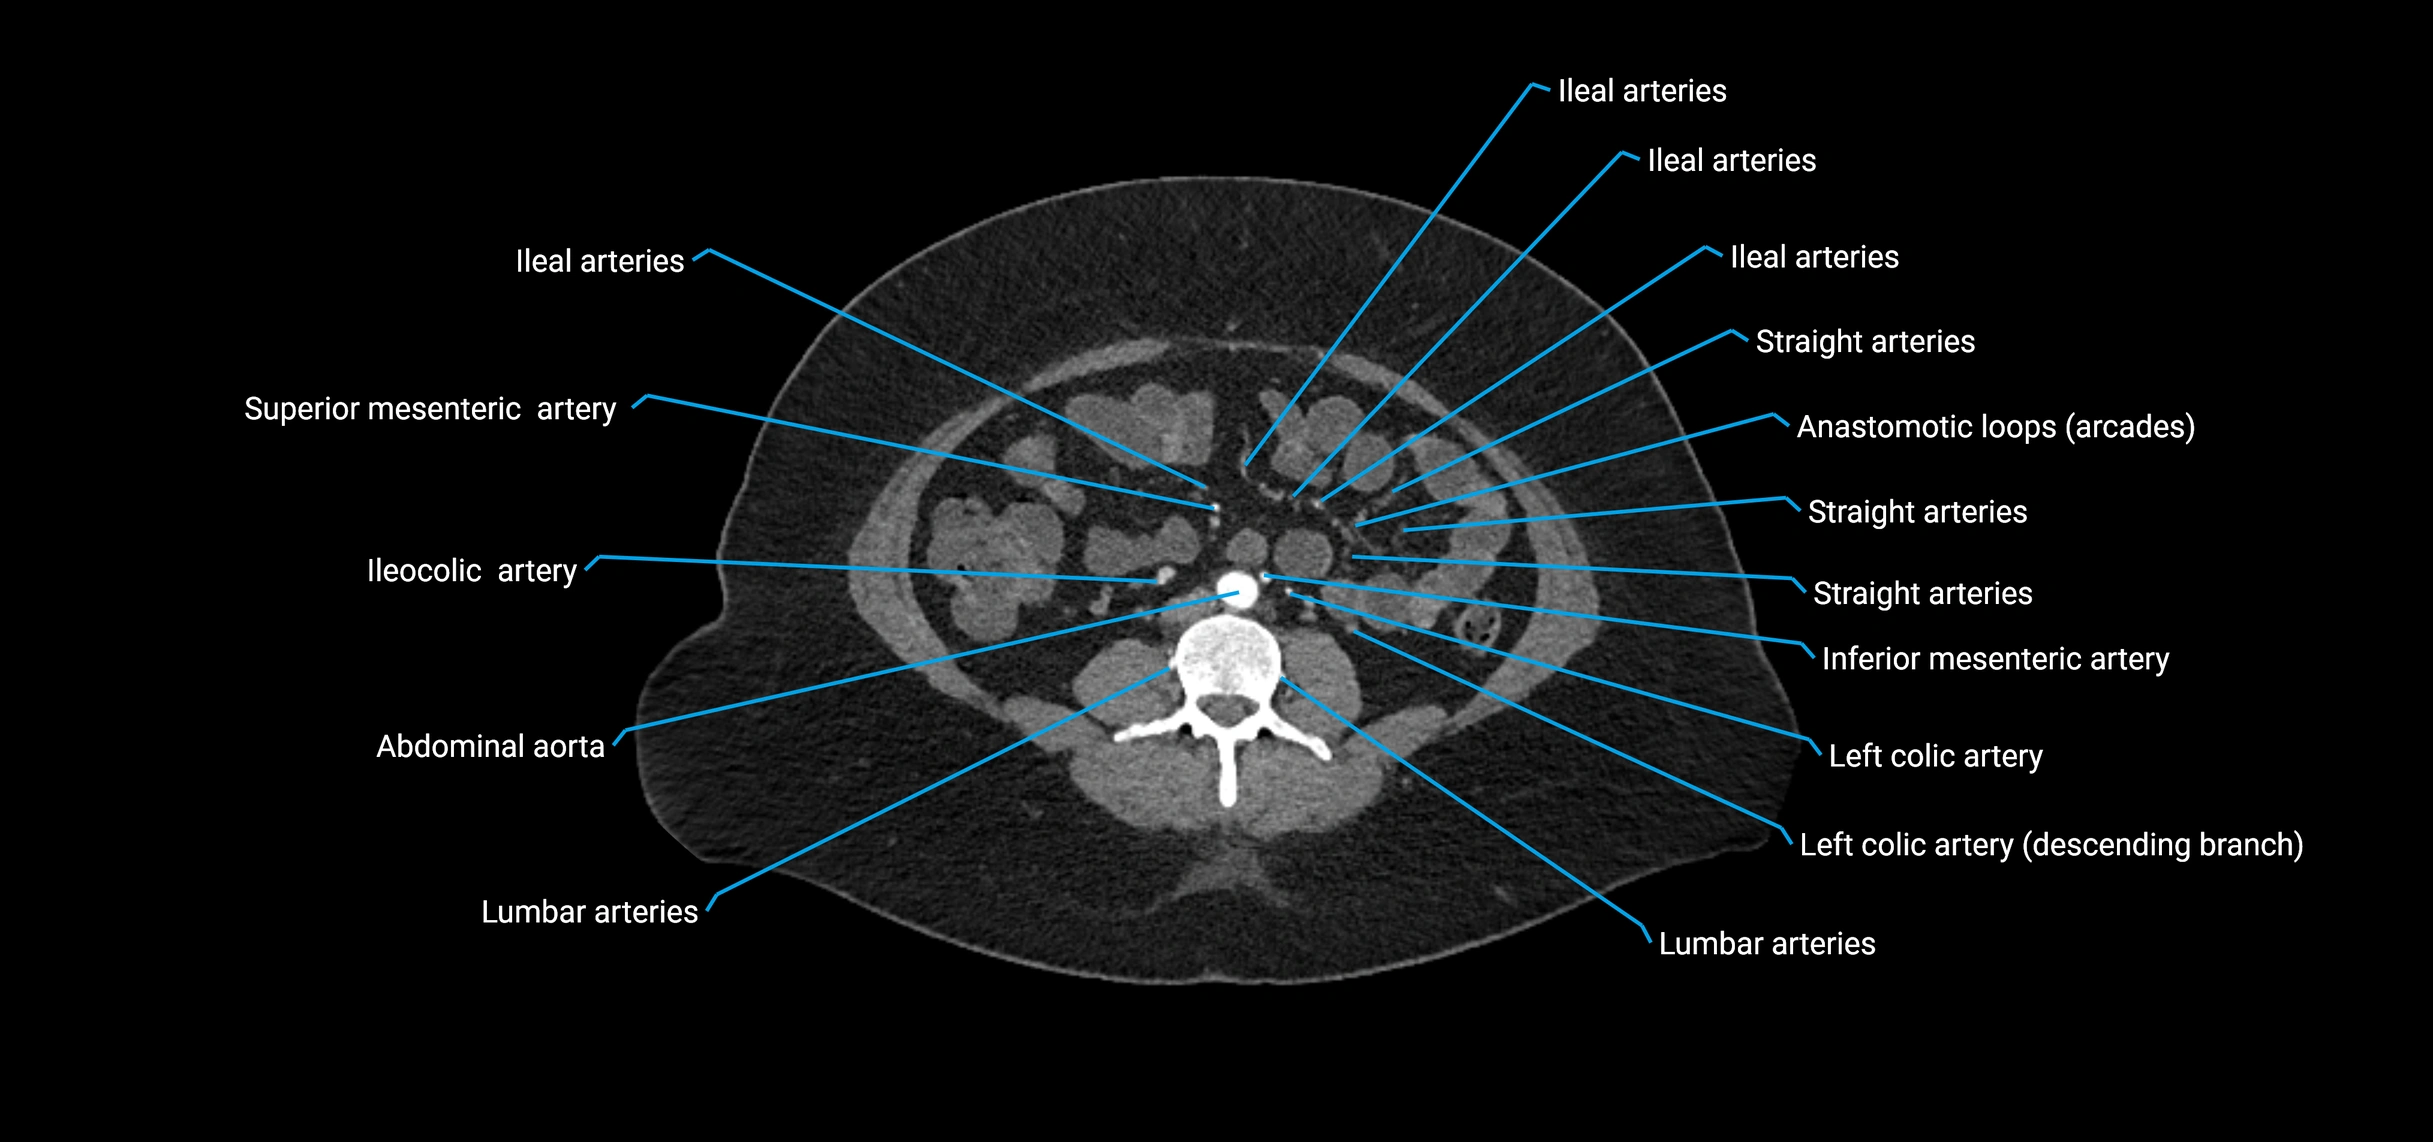

Contrast-enhanced CT (CTA):

• Gold standard for abdominal aortic imaging

• Provides excellent detail of lumen, wall, aneurysm, thrombus, and branch vessels

• Multiplanar and 3D reconstructions help in aneurysm measurement, stent graft planning, and dissection evaluation

• Detects acute rupture, traumatic injury, or occlusion with high sensitivity